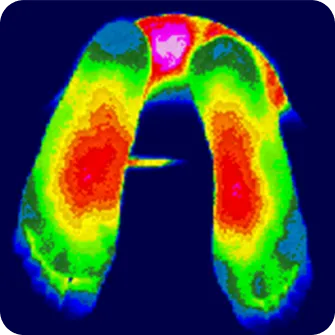

몸에서 발생하는 열에너지를 감지하여 눈에 보이지 않는 통증 부위와

신경이 손상된 부위를 찾아내고 진단하는 검사